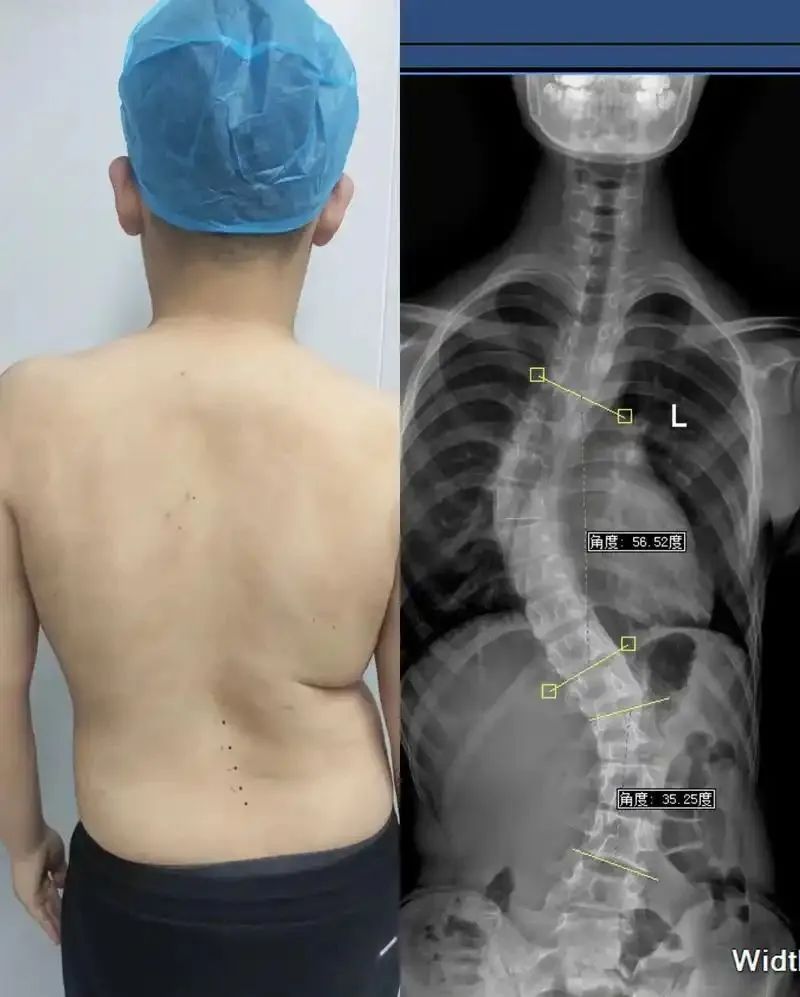

近些年,脊柱问题越来越严重,甚至越来越年轻化!

脊柱侧弯、脊柱炎、颈椎病、腰椎间盘突出...

现如今,有脊柱问题的人越来越多,脊柱病也越来越年轻化,而究其病因,很多都适合我们不良的生活习惯有关!

二郎腿、“葛优瘫”、躺着看手机、久坐、缺少运动...